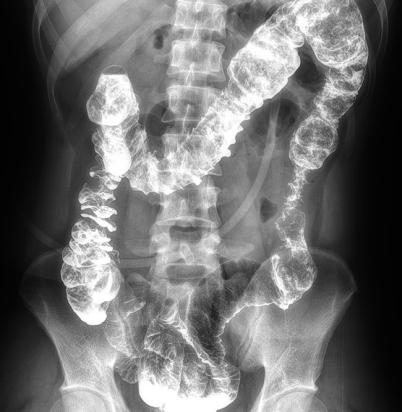

多功能動態(tài)平板DR,采用U型臂結(jié)構(gòu),具有靜態(tài)DR攝影、數(shù)字透視、數(shù)字造影和可視化攝影的功能。